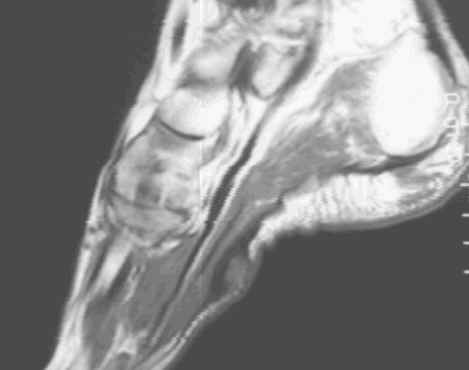

Characterized by nodular or poorly defined aggregates of mature to somewhat immature fibroblasts dispersed throughout dense collagen, causing irregular or nodular subcutaneous thickening of the plantar fascia. On MR, this appears as a nodular thickening of the plantar aponeurosis, which has low to intermediate signal intensity on both T1 and T2W images. Central increased signal intensity may be present.

62-year-old male with nodular thickening of the plantar fascia. This has intermediate signal on T1W and hyperintense signal on T2, proton density and Stir weighted images. These are atypical signal characteristics of plantar fibromatosis.